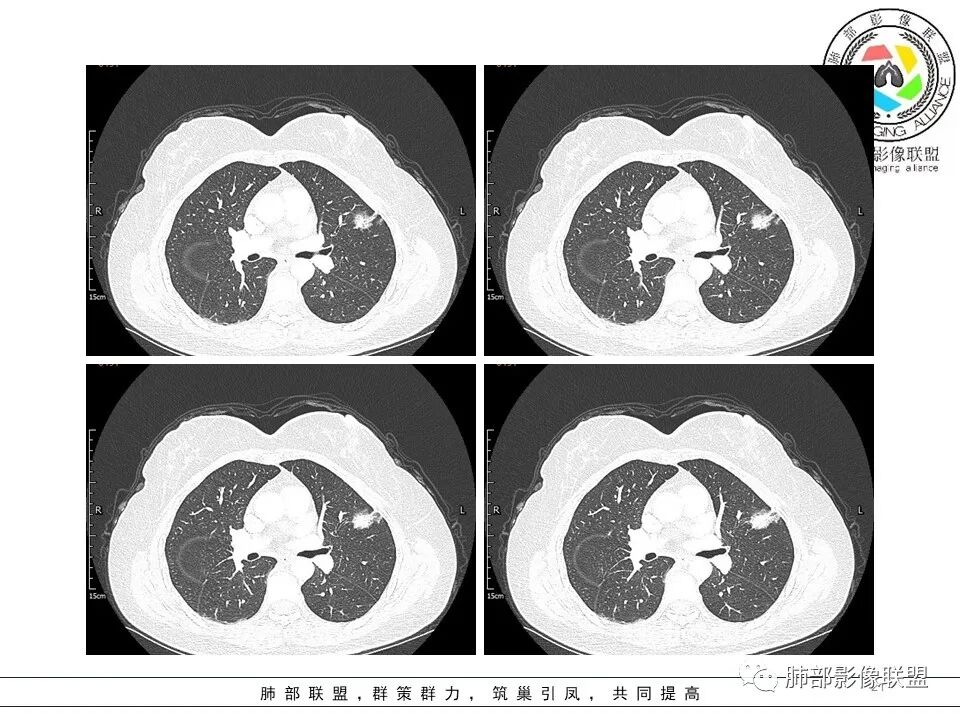

分叶结节,内部结构杂乱,边缘板刷样毛刺,GGO边界清楚

胸膜牵拉

月牙铲?

常规要考虑腺癌

一般半年无变化,边缘GGO

GGO的形成主要由:炎性渗出、出血、肿瘤侵犯

出血,半年会变化,炎性渗出也会变化

当然还有就是纤维化病变可以表现GGO

但是纤维化病变,边缘收缩,条带状为主

按理慢性炎性病变,比较特异性的——结核要放待排,因为结核是妖

1.病灶周围向几个方向膨出的边界清楚的磨玻璃影,这些磨玻璃影时隔几个月依然,几乎可以排除出血及一般的炎性改变。

2.病灶的胸膜牵拉线与其间病灶胸膜侧的磨玻璃边构成朝向胸壁的“月牙铲”结构,这种影像学表现某种程度上反映出病理学特征——病灶收缩+小叶间隔阻挡。

3.病灶实性密度区强化明显,这有助于我们区分一些其他类似病灶,如结核灶等!

结合临床,应当高度怀疑浸润性肺腺癌!